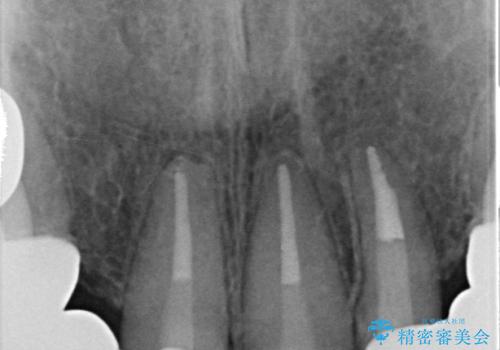

左上4番目の歯から右上3番目の歯まで計7歯のクラウンを除去し、オールセラミッククラウンによる補綴を行いました。

根管治療の注意事項(リスク・副作用など)

- 根管治療により類似の全ての症例の問題が解決するわけではなく、症例はあくまでも一例です

- 根管治療により痛みや腫れがひかない事や、術後に痛みや腫れが生じる事、治療によるファイル破折やパーフォレーションなどの偶発症、術後の歯根破折を生じる可能性もあります